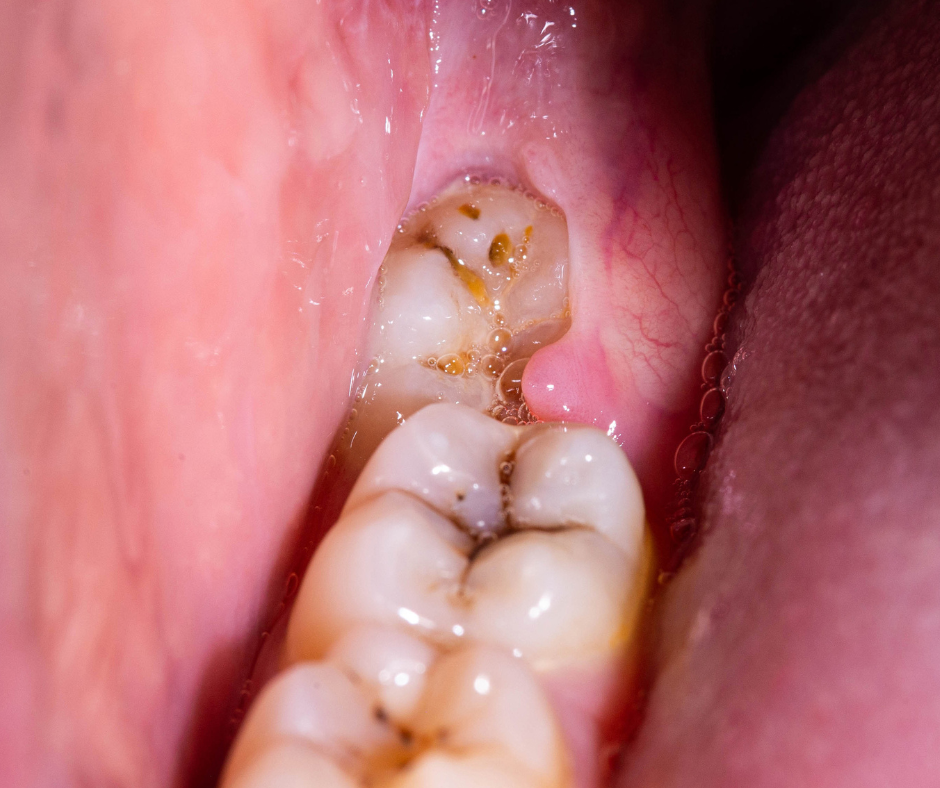

1) Gum infection (Pericoronitis)

When the impacted wisdom tooth is partially covered by gums, food might get easily stuck between the gums overlying the wisdom tooth and the tooth itself. Food stuck at the impacted wisdom tooth are usually not easily accessible for tooh brushing. As a result, gum infection will occur and this causes pain, swelling, pus discharge at the area.